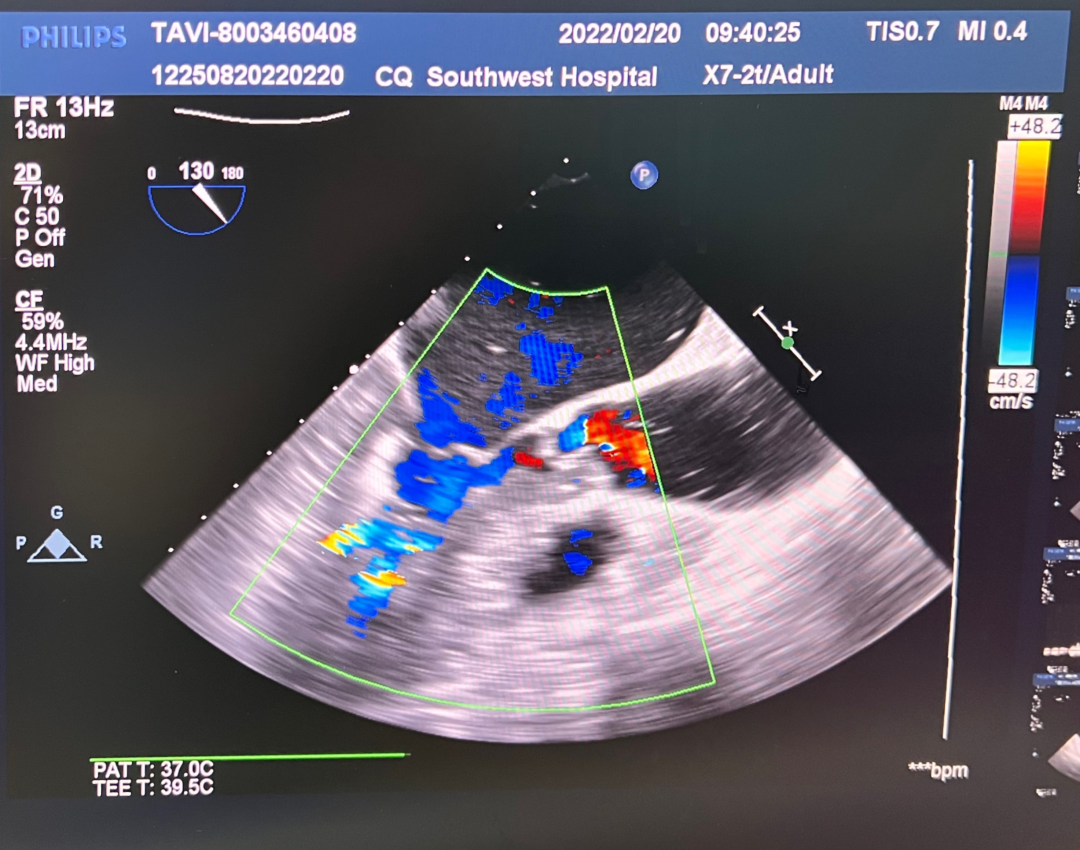

术后即刻评估

术后平均压差在5mmHg左右,几乎无反流,瓣膜正常工作。